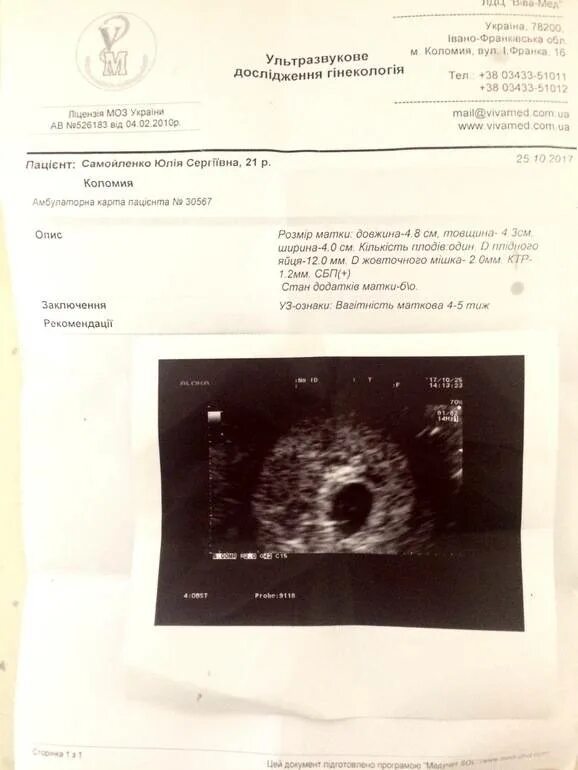

На 4 неделе беременности узи покажет беременность